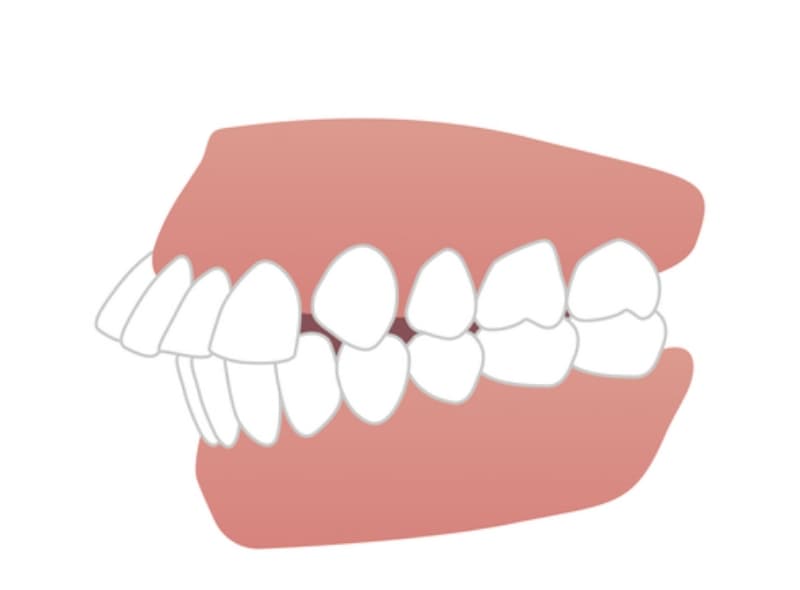

上顎前突

上の前歯が下の前歯に比べて著しく前に出ている状態です。上顎前突は、口唇の閉鎖不全や口呼吸、発音の問題などを引き起こすことがあります。また、前歯の突き上げや外傷のリスクも高くなります。

下顎前突

下の前歯が上の前歯よりも前方に位置している状態で、「受け口」とも呼ばれます。下顎前突は、かみ合わせの不調和や顎関節症、咀嚼機能の低下などを引き起こす可能性があります。